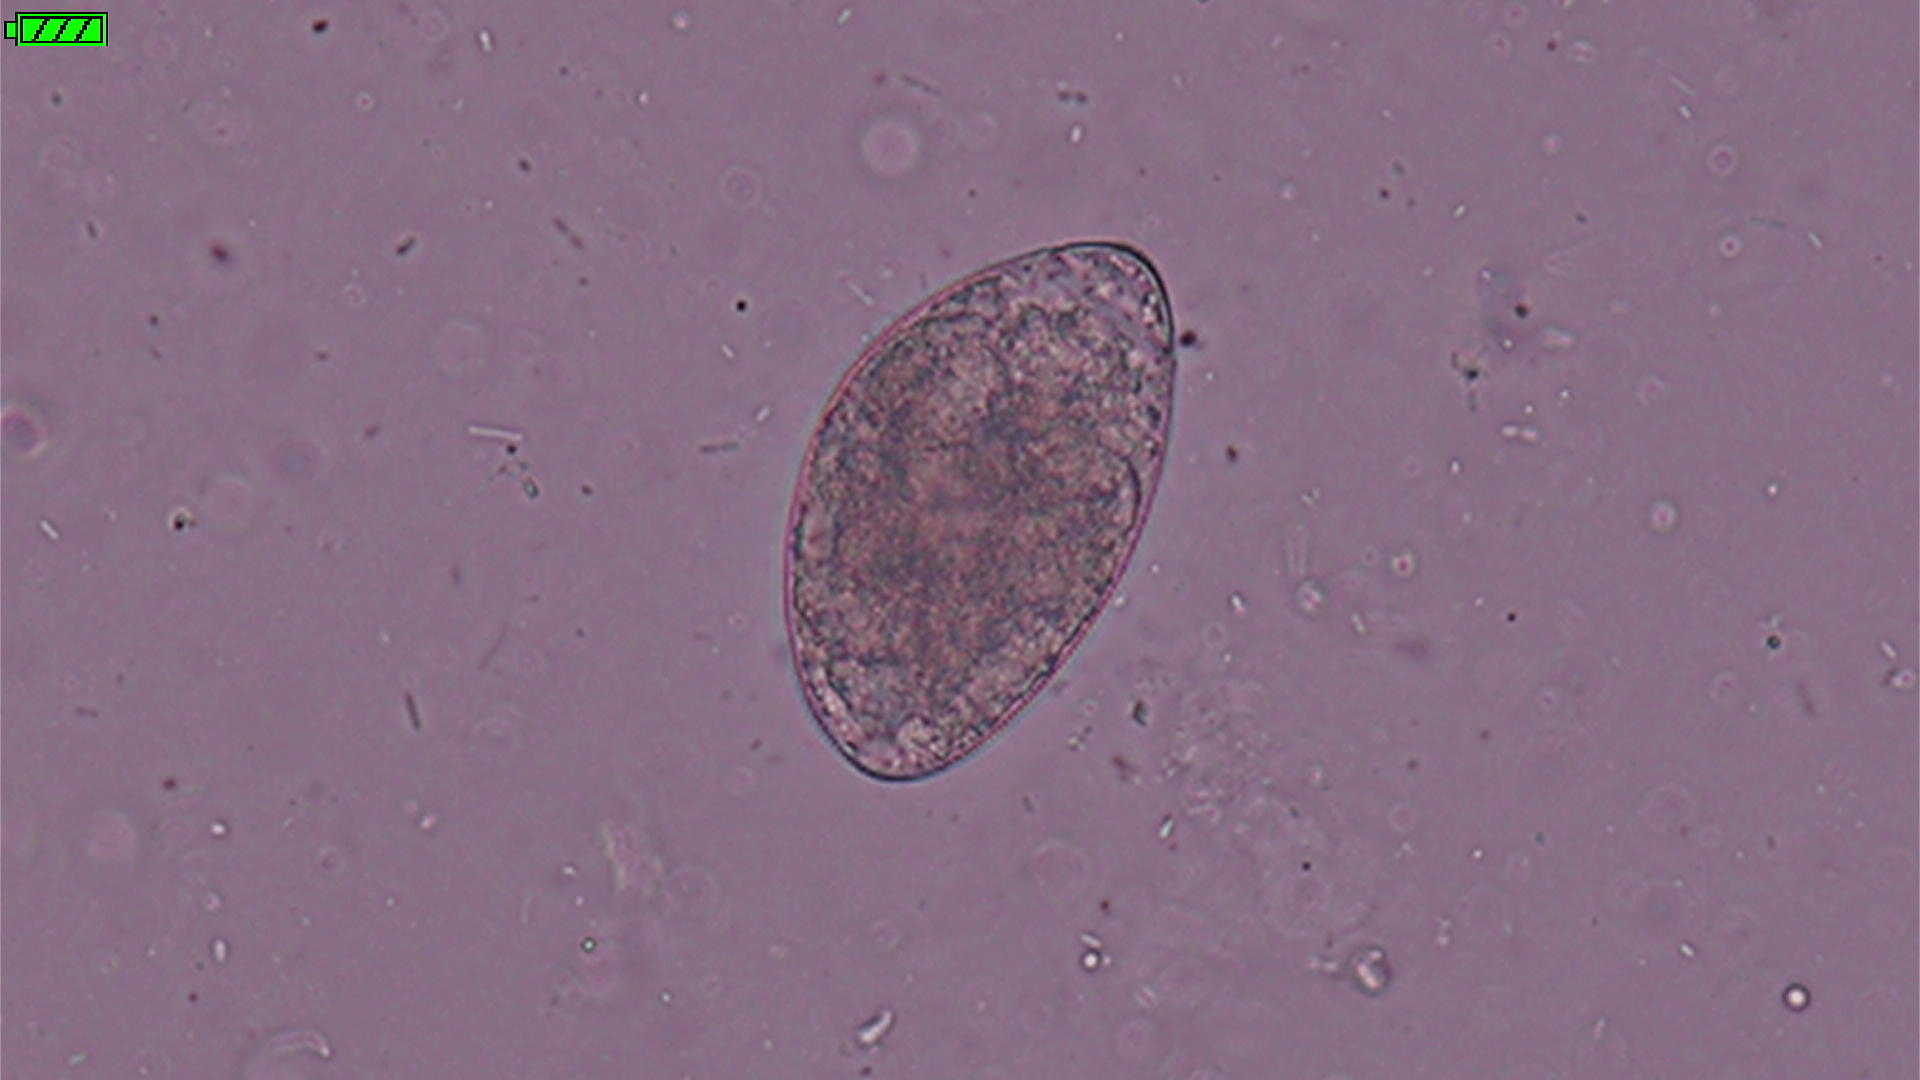

みなさんはこのような寄生虫を見たことがありますか?

この寄生虫、名称は「マンソン裂頭条虫」というサナダムシの一種で、猫や犬の小腸に寄生します。

この虫卵は水中でふ化し、遊泳幼虫としてケンミジンコ(第1中間宿主)に入ります。